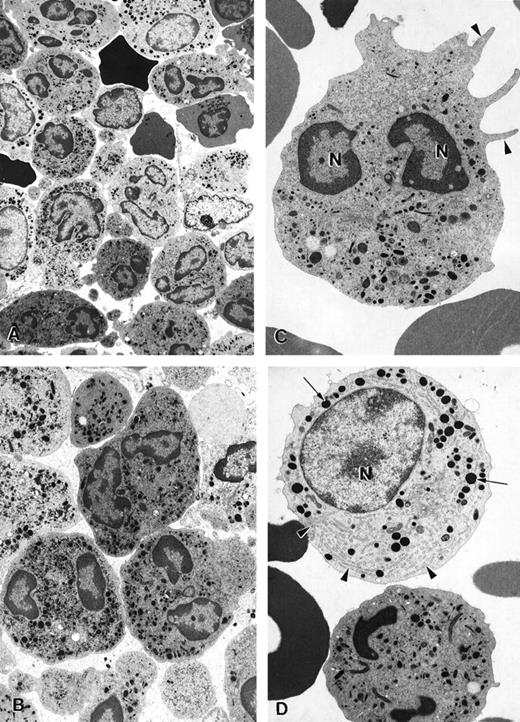

Before G-CSF treatment, approximately 55% of peripheral blood neutrophils from patient 2 underwent spontaneous apoptosis during storage overnight in vitro. In contrast, only 10% apoptosis was observed in neutrophils from a healthy volunteer. During G-CSF treatment in vivo, the percentage of neutrophils from the patient with myelokathexis undergoing spontaneous apoptosis was substantially reduced. A similar effect of G-CSF treatment was observed for bone marrow cells in myelokathexis. During G-CSF treatment, the patient's bone marrow clearly contained fewer apoptotic neutrophils, as determined by electron microscopy (Figure7A). Round neutrophils, microvilli on the cell surface, and typically polymorphous nuclei were observed. Promyelocytes and an increased number of mature neutrophils were present, indicating the influence of G-CSF treatment (Figures 7B, 7C).

Electron micrographs of bone marrow cells from a myelokathexis patient 2 during granulocyte colony-stimulating factor treatment.

(A) Low-magnification image of bone marrow shows numerous differentiated neutrophils. Magnification ×3750. (B) Mature neutrophils in bone marrow observed at higher magnification appear normal and show negligible evidence of apoptosis. Magnification ×5000. (C) Mature neutrophil shows typical microvillar structures (arrowheads) on the cell surface. Nuclear lobes (N) appear normal and show regular chromatin distribution. Magnification ×7000. (D) Mature neutrophil (bottom) and promyelocyte (top) in the bone marrow. The promyelocyte contains extensive rough endoplasmic reticulum (arrowheads) and electron-dense granules (arrows). N, nucleus. Magnification ×7000.